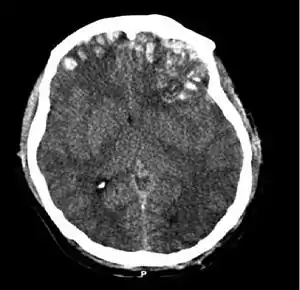

| CT scan showing cerebral contusions, hemorrhage within the hemispheres, subdural hematoma, and skull fractures[2] | |